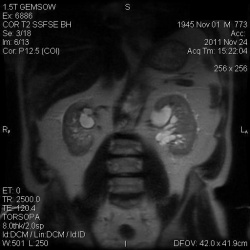

25.07.2013 - 00:24

.Метастатическое поражение лимфатических узлов и брюшины малого таза. Гиперплазия эндометрия. Асцит.